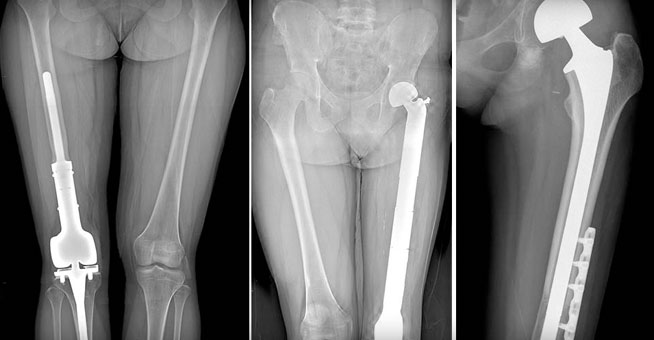

병기결정을 위해 시행하는 검사는

X-ray(가장처음), MRI, bonescan, chest CT, PET-CT, biopsy(마지막 검사) 등이 있습니다.